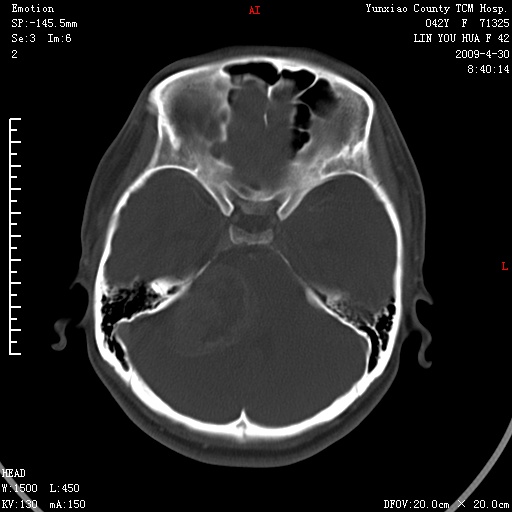

右侧桥小脑角区肿瘤,高密度囊变有显著强化,骨窗见内听道显著扩大,考虑听神经瘤可能性大

内听道扩大,支持考虑听神经瘤可能性大。